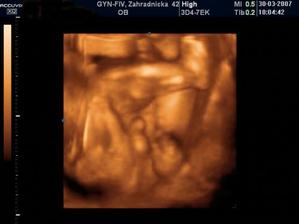

Nathan Nicolas ! bruško, pôrod a prvé mesiace

Nathan Nicolas, narodil sa v Bojnickej pôrodnici, v piatok 13. júla ráno 8:08... Mal 3020 g, 50 cm a spolu so svojim starším bratom je to najväčšie šťastie 🙂